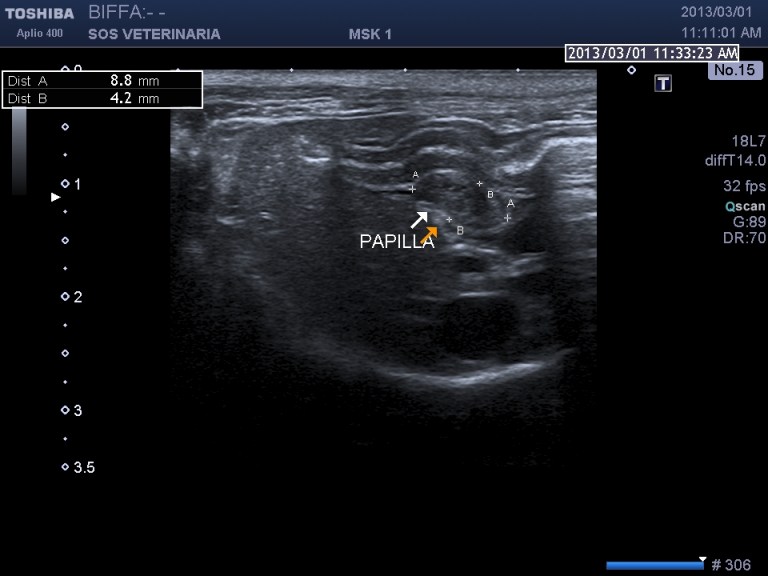

PROCESSO INFILTRATIVO DUODENALE E DELLA PAPILLA  (infiammatorio o neoplastico)

gatto comune europeo 9 aa ABC_8738

Le vie biliari del gatto hanno caratteristiche diverse rispetto al cane il dotto pancreatico principale raggiunge il coledoco  prima che questo defluisca nella papilla duodenale maggiore (nel cane lo sbocco e’ indipendente) ,inoltre il dotto accessorio  sfocia nella papilla minore ,un processo ostruttivo distale porta quindi a distensione  di entrambe le componenti  ,l’iperplasia della parete delle vie biliari  puo’ essere indicativa di flogosi o di cronicita’ dell’ostruzione  (in questo caso la parete e’ normale) ma come sopraesposto la diagnosi richiede spesso invasivita’ ,questo caso purtroppo  non ha seguito nessuna diagnosi ,il soggetto non ha risposto alla terapia cortisonica (l’unica che ha voluto tentare il proprietario) e antibiotica e si e’ perso nel foll’up, Una laparotomia esplorativa con campionamento del tessuto iperplastico  e coltura biliare era a mio avviso unica opzione possibile per una corretta diagnosi .

Il caso si mostra interessante sul piano dell’imaging che evidenzia la complessita’ delle vie biliari extraepatiche e pancreatiche dilatate.

Durante l’esame delle strutture biliari può venire identificata la papilla duodenale le cui dimensioni, nei gatti sani, variano dai 2,9 a 5,5 mm in larghezza ed una massima altezza di 4,0 mm, in sezione trasversa; nel cane le sue dimensioni sembrano essere maggiormente variabili, in relazione alle differenze di peso e di razza (Center S.A., 2009).”

scansione trasversale papilla

scansione sagittale paipilla